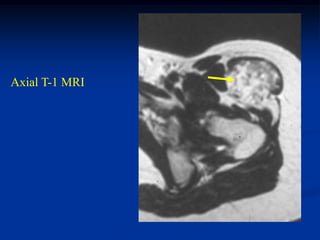

Case #1188 72 yearfemale with intramuscular lipoma mid arm

Case #1189 2 yearmale with intramuscular lipoma posterior thigh